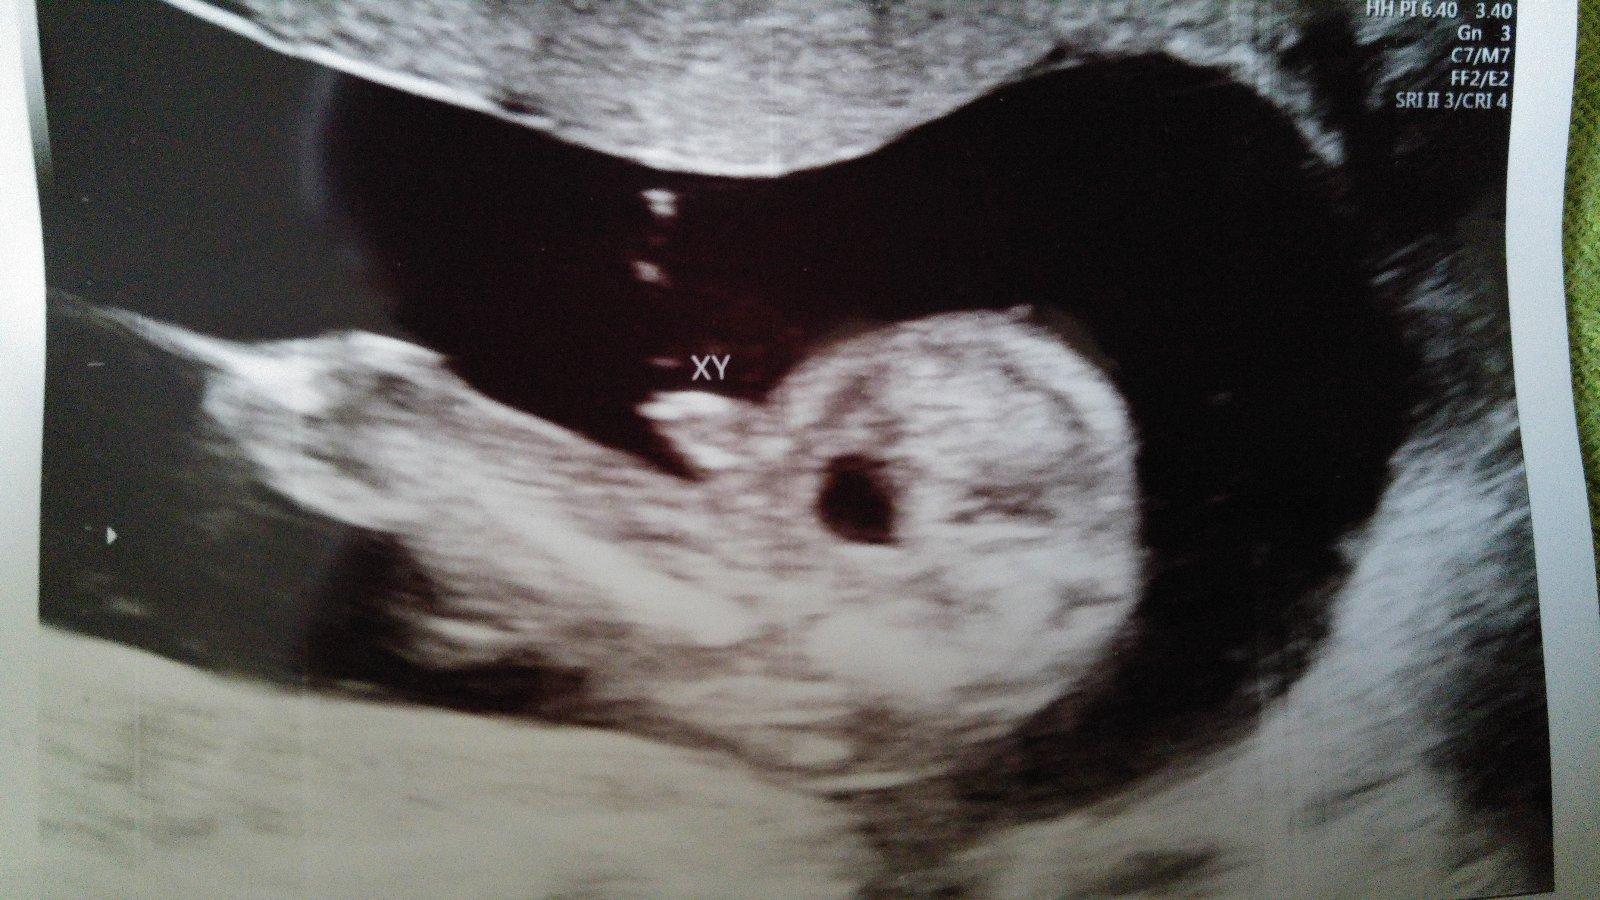

Naš pokladík 🙂 na 2 fotke vidieť pinďulíka 🙂